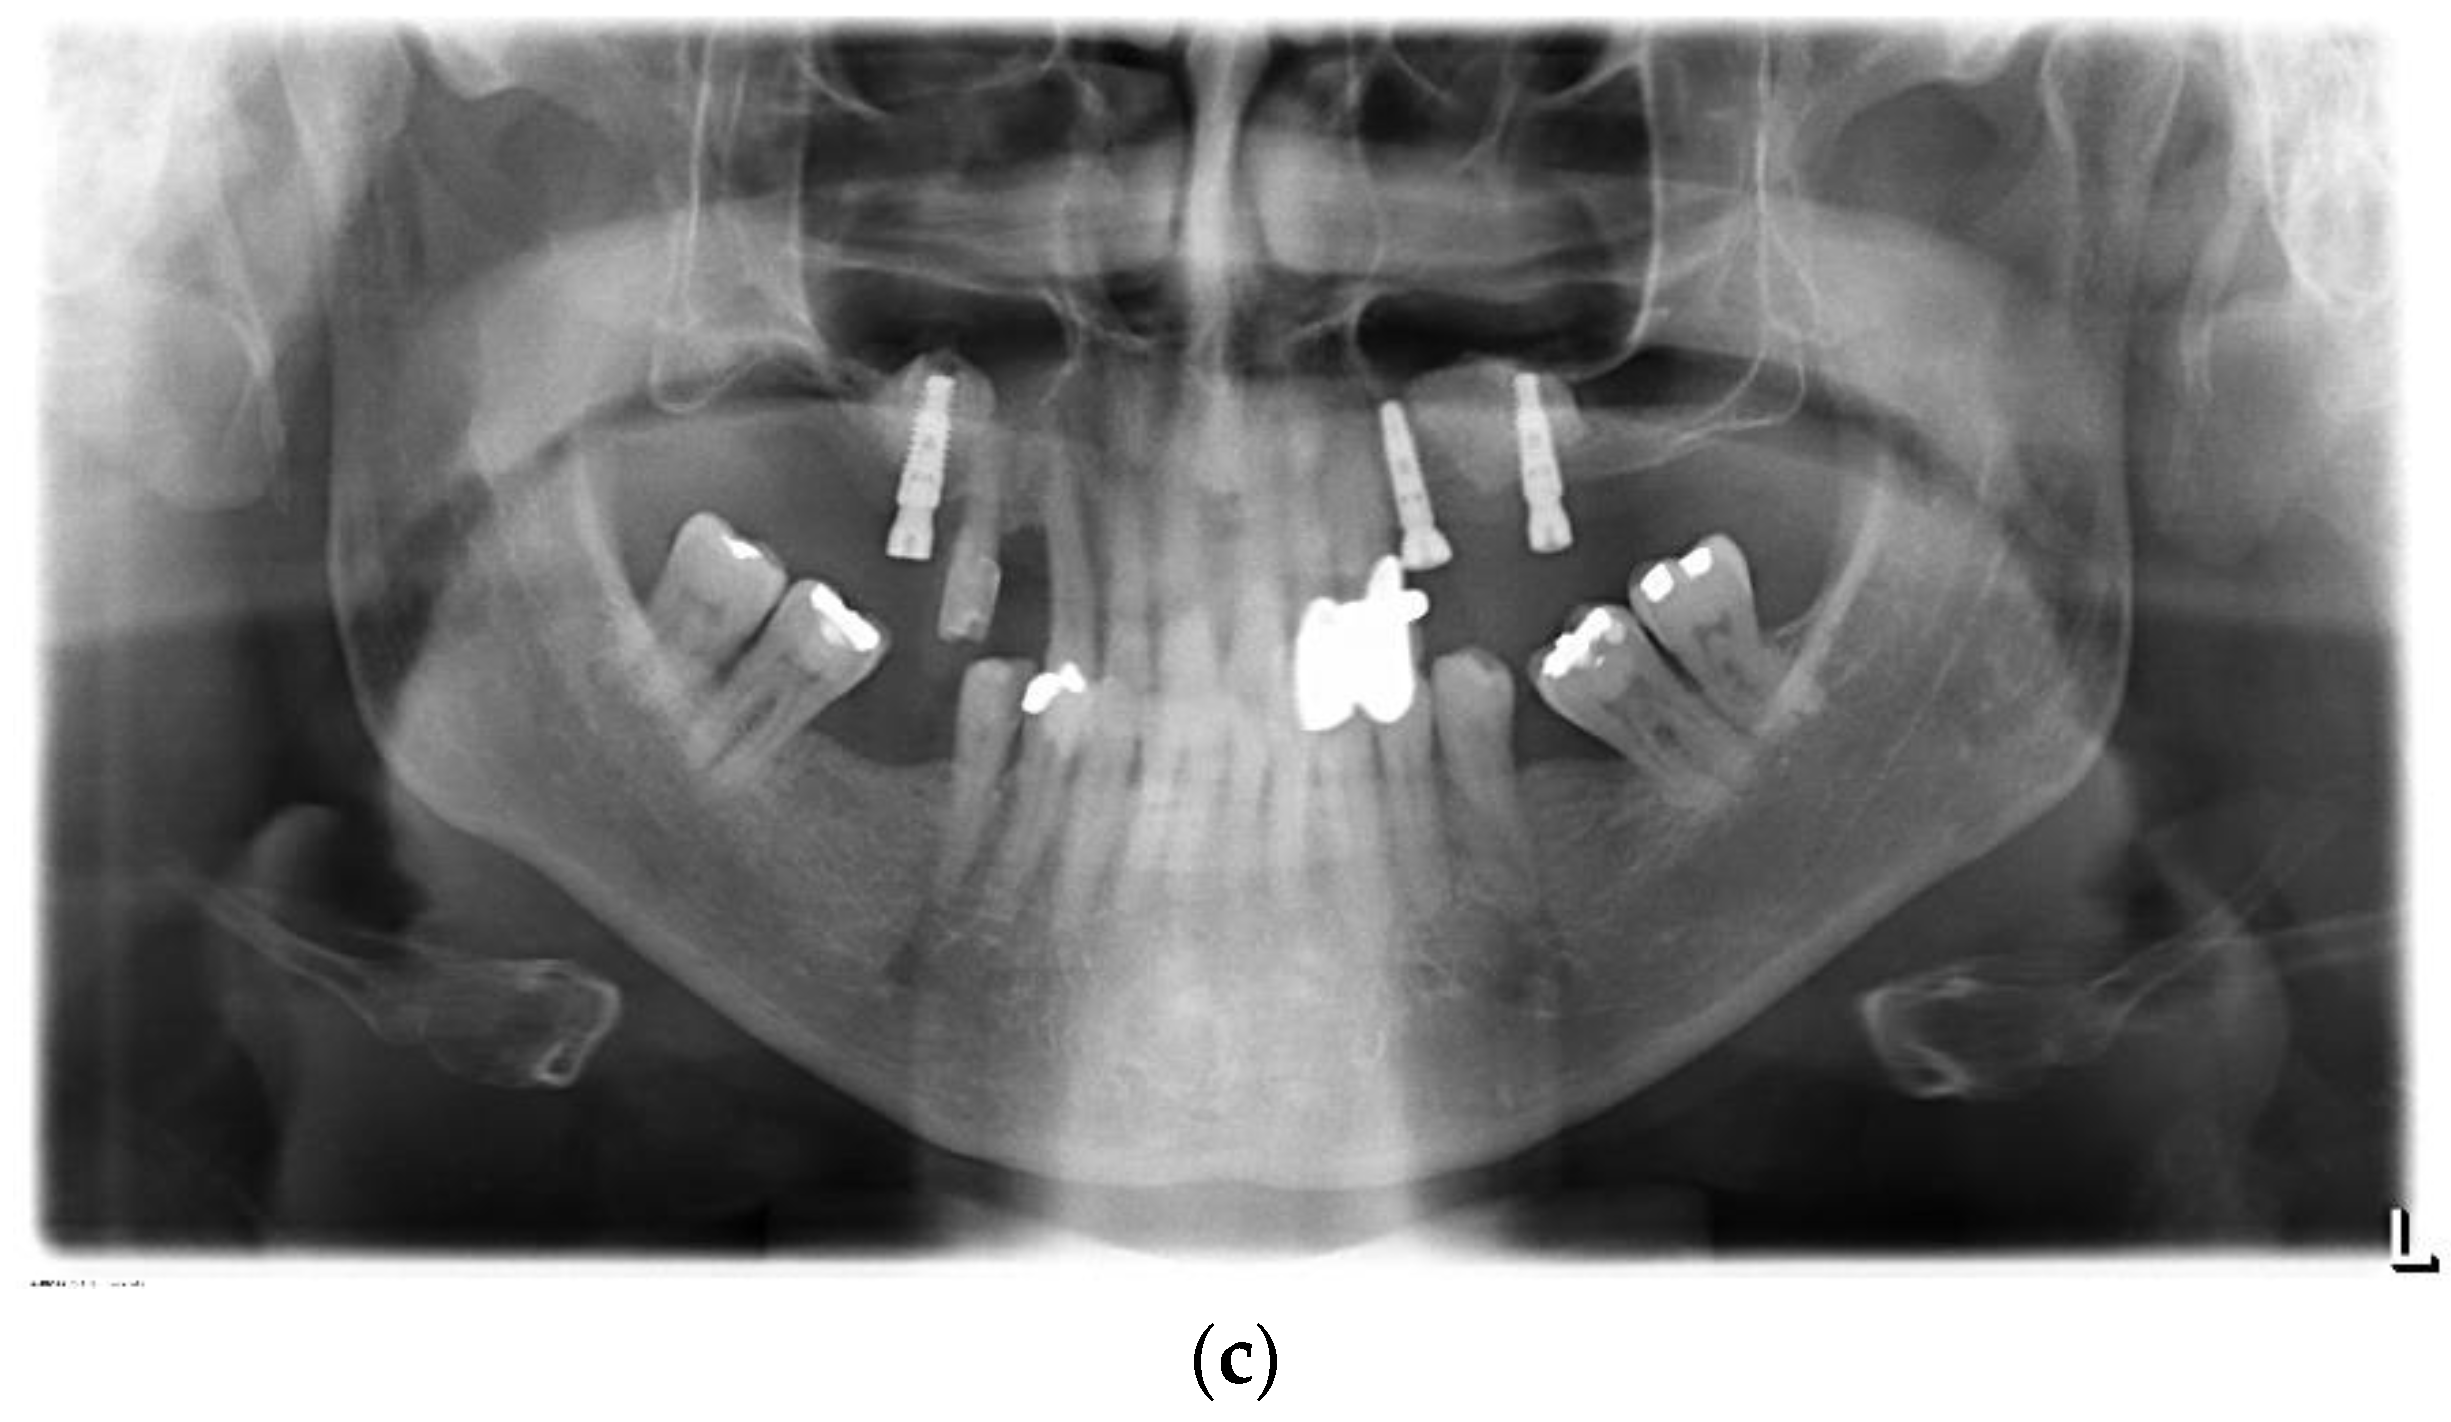

3.2. Radiographical Outcome